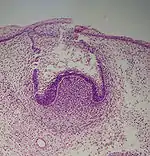

A: enamel organ

B: dental papilla

C: dental follicle

The tooth germ is an aggregation of cells that eventually forms a tooth.[2] These cells are derived from the ectoderm of the first pharyngeal arch and the ectomesenchyme of the neural crest.[1][3][4] The tooth germ is organized into three parts: the enamel organ, the dental papilla and the dental sac or follicle.

The first signs of an arrangement of cells in the tooth bud occur in the cap stage. A small group of ectomesenchymal cells stops producing extracellular substances, which results in an aggregation of these cells called the dental papilla. At this point, the tooth bud grows around the ectomesenchymal aggregation, taking on the appearance of a cap, and becomes the enamel (or dental) organ covering the dental papilla. A condensation of ectomesenchymal cells called the dental sac or follicle surrounds the enamel organ and limits the dental papilla. Eventually, the enamel organ will produce enamel, the dental papilla will produce dentin and pulp, and the dental sac will produce all the supporting structures of a tooth, the periodontium.[1]